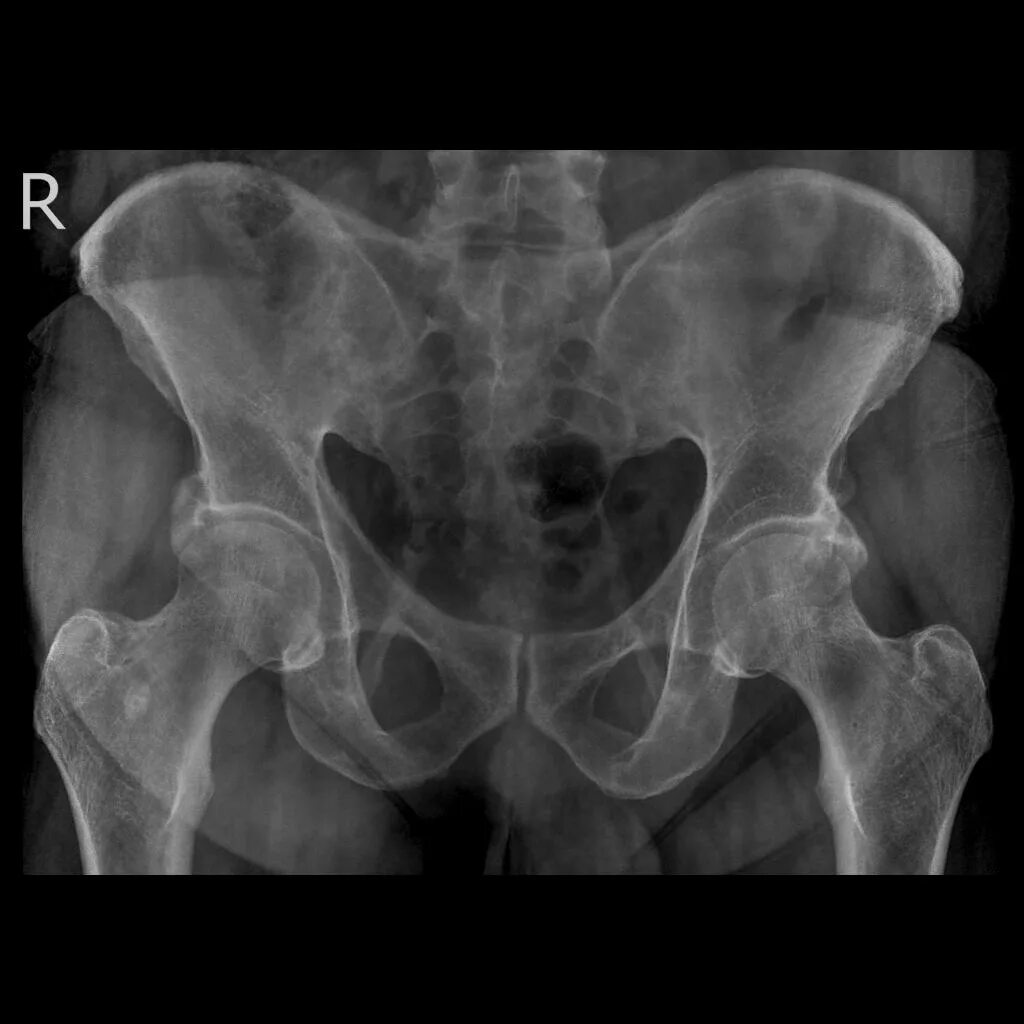

Метастазы в крестце